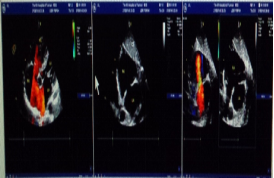

病歷資料 患者,男性,50歲,因“反復(fù)上腹部疼痛4月余,再發(fā)加重伴醬油色尿1周”入院。查體:血壓 113/70mmHg,心率 50次/分,精神差,少言懶語。全身皮膚及鞏膜輕度黃染,雙肺呼吸音粗,未聞及干濕性啰音。心尖搏動在左第六肋間鎖骨中線外1cm,心界向左下擴(kuò)大,各瓣膜聽診區(qū)未聞及病理性雜音。腹部平坦,劍突下及右上腹部壓痛明顯,Murphy征陽性。雙下肢無水腫。初步診斷:1.溶血性黃疸?2.先天性心臟病,房間隔缺損封堵術(shù)后,心臟擴(kuò)大,心功能III級;1月前在當(dāng)?shù)蒯t(yī)院行心彩(圖1)檢查:先天性心臟病,房間隔缺損(ASD),缺損直徑為21 mm,房水平左向右分流;估測肺動脈收縮壓72mmHg,在局麻下行“經(jīng)皮穿刺ASD 封堵術(shù)”,選擇直徑32mm,(先建科技公司)雙盤ASD封堵器采取左上肺靜脈釋放法,一次封堵成功。封堵后即可測肺動脈收縮壓為65mmHg。術(shù)后復(fù)查超聲未發(fā)現(xiàn)殘余分流。術(shù)后1月患者突然出現(xiàn)乏力、納差、醬油色尿。尿常規(guī): 尿膽原(-),隱血+++,尿蛋白+++,膽紅素+,白細(xì)胞+, 提示血紅蛋白尿;血常規(guī):WBC 11.13*10^9/L,RBC 3.47*10^12/L,HBG 79g/L,PLT 232*10^9/L;肝功能:TBI 3.4umol/L,DBI 5.9umol/L,IBI 57.5umol/L,GPT 83U/L,AST 165U/L。心電圖:竇性心律,完全性右束支傳導(dǎo)阻滯。入我院后復(fù)查心彩(圖2):1.房間隔缺損封堵術(shù)后,封堵器周圍未見異常血流信號;2.右心擴(kuò)大,肺動脈內(nèi)徑增寬,輕度肺動脈高壓;肺動脈瓣、三尖瓣少量反流。完善溶血全套、CD55、CD59、骨髓細(xì)胞學(xué)檢查,Coombs試驗(yàn)陰性, 除外自身免疫性溶血,Ham試驗(yàn)陰性,陣發(fā)性睡眠性血紅蛋白尿可能性小。Rous試驗(yàn)陽性,提示血管內(nèi)溶血。雖然復(fù)查心彩封堵器周圍未見異常血流信號,但仍不能排外因封堵器原因造成機(jī)械性溶。立即給予停用拜阿司匹林、大劑量糖皮質(zhì)激素(甲潑尼龍80mg/天)、輸入洗滌紅細(xì)胞、抗感染治療、碳酸氫鈉堿化尿液等對癥支持治療。治療20天后患者腹痛、乏力、納差明顯好轉(zhuǎn),小便顏色逐漸轉(zhuǎn)清,HBG 113g/g;尿常規(guī)、血生化正常,好轉(zhuǎn)出院。